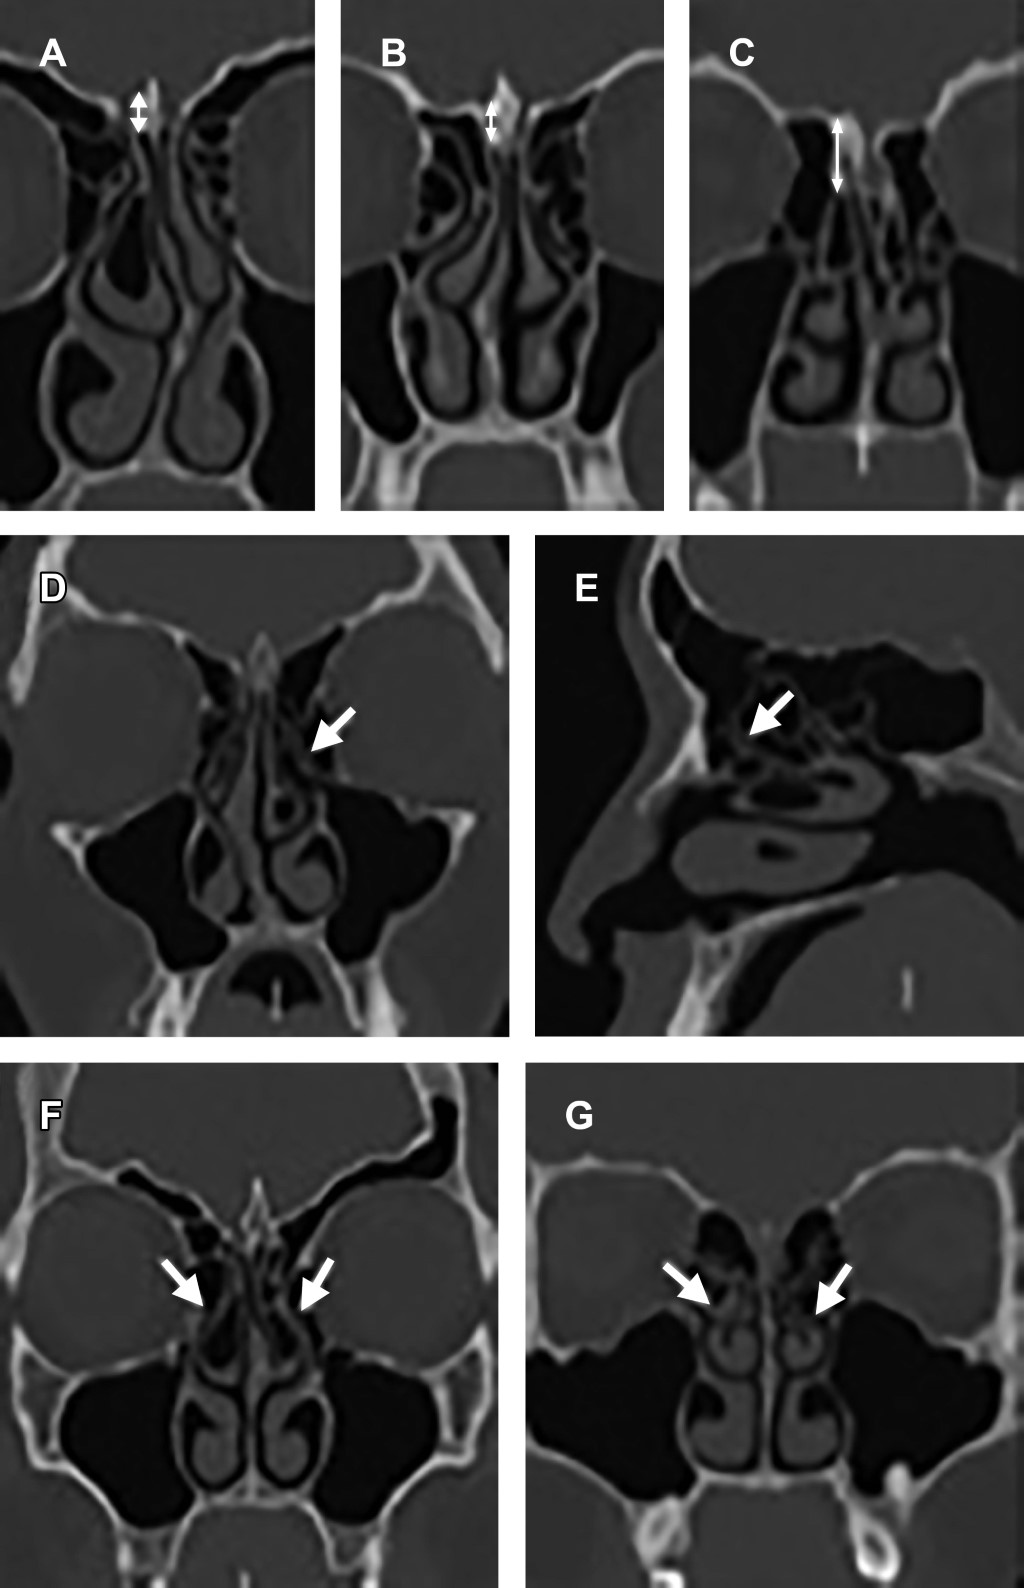

Para la profundidad de la fosa olfatoria, definida como relación vertical entre la lámina cribosa y techo etmoidal, se utilizó la clasificación de Keros (Figura 2). El más frecuentemente visualizado fue el tipo 2 con 59%, luego tipo 3 20% y por último el tipo 1 en 21%.

Se identificó neumatización de cornete medio (a nivel del bulbo, lamela o ambas) en 60% al menos de forma unilateral. El giro paradójico de cornete medio, en el que la convexidad se proyecta hacia la línea media, se observó en 68% de los estudios al menos de forma unilateral (Figura 2).

La profundidad de fosa olfatoria (equivalente a la longitud de la lamela lateral), comprende tres tipos de acuerdo a la clasificación de Keros según la relación vertical entre la lámina cribosa y techo etmoidal medida en plano coronal.2 Se estima que la prevalencia en población general para el tipo 1 es de 30%, tipo 2 de 49% y tipo 3 de 21%, similar a lo encontrado en los estudios, siendo de 21, 59 y 20% respectivamente. Los tipos 1 y 3 presentan mayor riesgo de lesión iatrogénica, destacando meningitis, fístula de LCR y encefalocele, por comunicación de compartimento intracraneal a cavidades sinusales.2,3 Por lo que, en conjunto, los tipos 1 y 3 corresponden a 41% de los pacientes.

Los cornetes medios presentan una gran variedad de variantes anatómicas. En población general, se identifica su neumatización en aproximadamente 15-35% según el segmento involucrado (lamelar, bulbar o ambas). El giro paradójico se observa en 3 a 30% de los pacientes. Para este estudio se consideró como presente la neumatización de cualquier segmento del cornete al menos de forma unilateral. El giro paradójico se definió como convexidad de orientación medial, considerándose presente al menos de forma unilateral. Fueron visualizadas en 40 y 32% de los pacientes respectivamente.